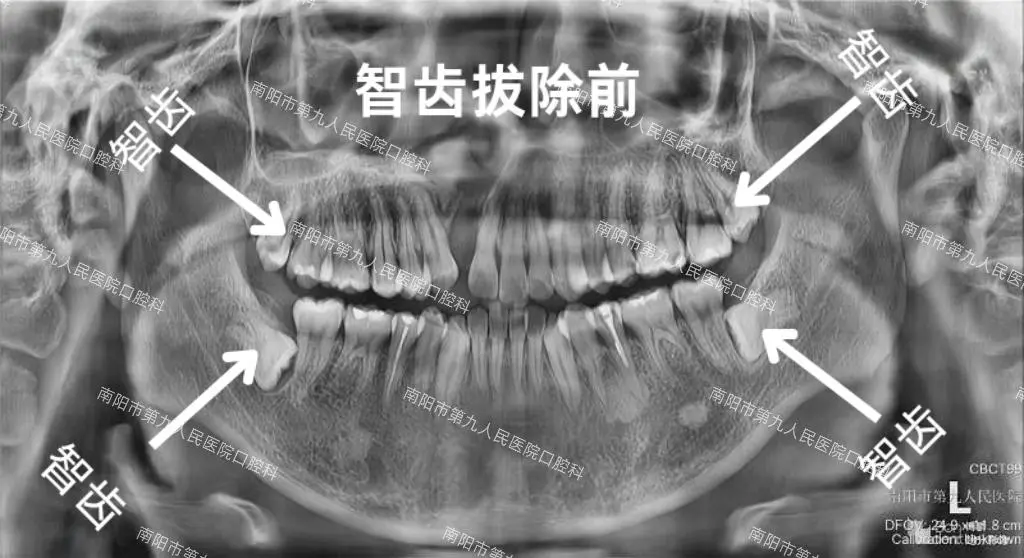

患者儿子智齿拔除前后X光对比图

患者朋友说:“这次孩子的体验,却完全颠覆了我对‘拔牙’的恐惧:李医生会一步步和孩子解释流程,安抚他的紧张情绪,连一向怕看牙的孩子事后都拉着我说‘医生叔叔好温柔’。整个过程是微创的,孩子说全程几乎没有痛感,拔完也没有明显的肿胀。更让我们安心的是,结束后李医生还特意叮嘱了术后护理的细节,比如怎么冰敷、吃什么食物更合适。”